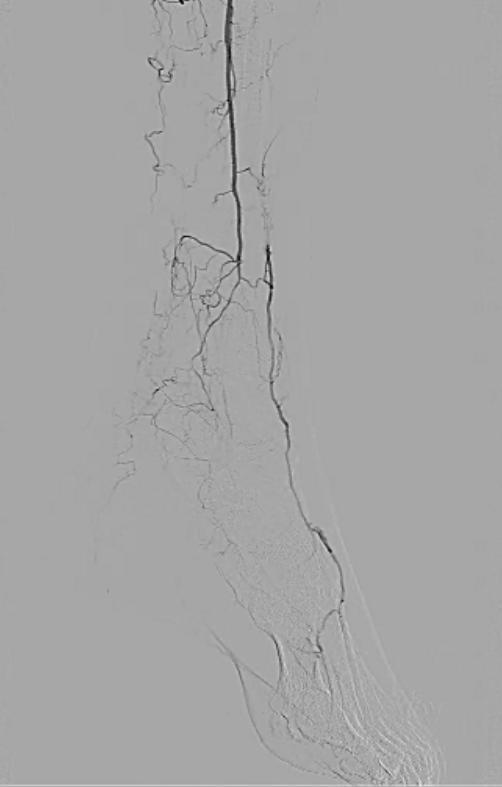

Angioplasty of the left tibial arteries was performed for limb salvage. With support from a 6F 65 cm sheath via the right common femoral artery, a 3×20 mm balloon was used for angioplasty of the left tibioperoneal trunk. A 0.018 inch Confianza Pro 12 wire (Abbott Vascular, Abbott Park, IL) and support catheter was used to cross the occluded anterior tibial artery, which was then angioplastied with multiple inflations of a 3×100 mm balloon, producing a good result (Figure 4):